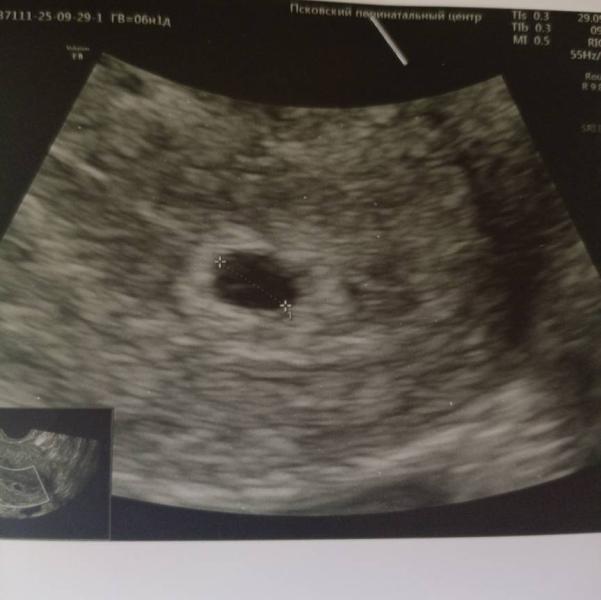

Только плодное яйцо на 6 неделях - нормально ли это?

Была на узи по кд 6'2 на узи только плодное яйцо не жм не чсс естественно... Ожидаю дальше

@_dayana_ у вас слева точно что то есть, на колечко похоже, уверена у вас все хорошо будет☺️